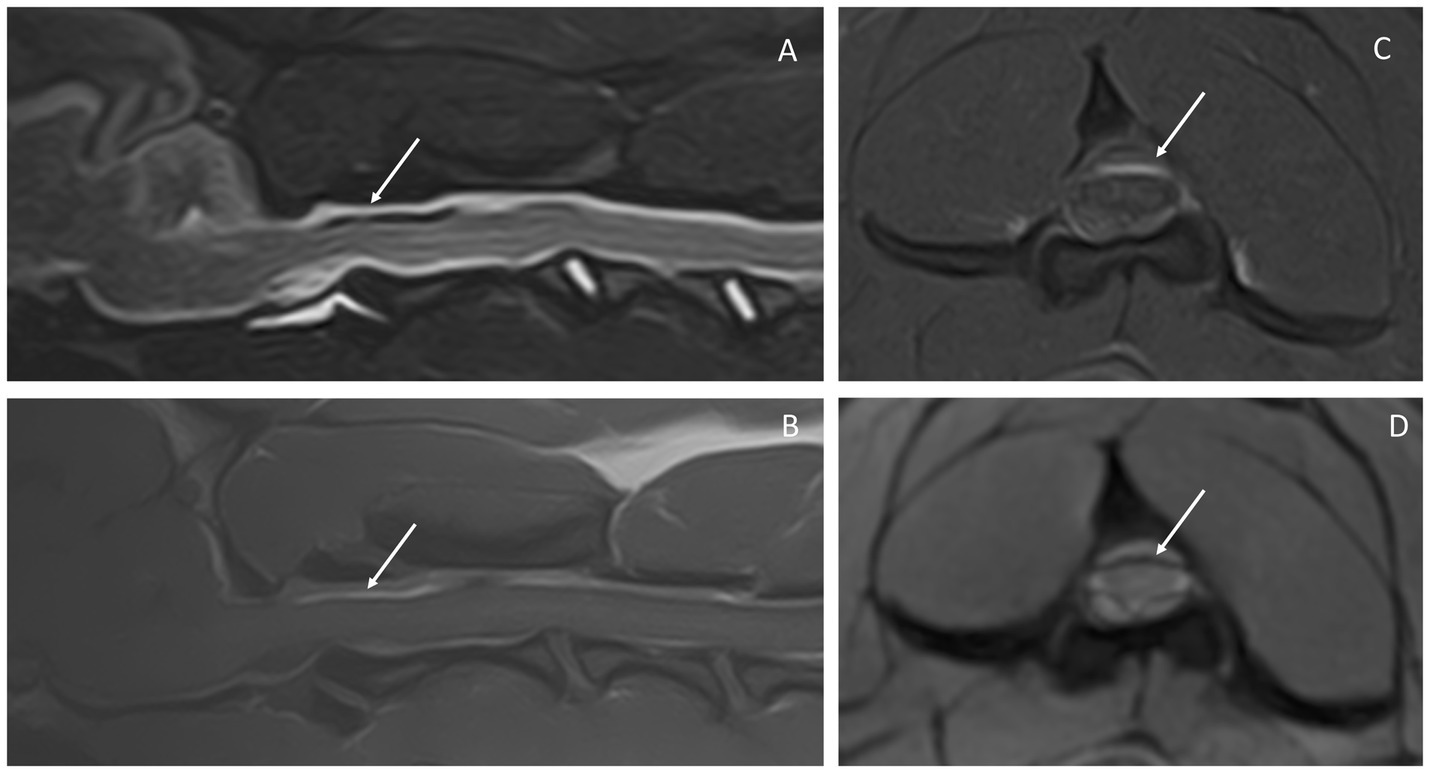

Un Staffordshire terrier intacto macho de 1 año, nacido y criado en los Países Bajos, se presentó con una historia de 3 semanas de letargo progresivo e hiperestesia espinal, predominantemente cervical. Aparte de la hipertermia y la hiperestesia cervical, el examen general y neurológico no reveló ninguna anomalía. Las pruebas hematológicas y bioquímicas completas se consideraron normales. La resonancia magnética de la región craneocervical reveló heterogeneidad del espacio subaracnoideo, caracterizada por una hiperintensidad de T1W previa al contraste, correspondiente a un vacío de señal T2*. Desde la fosa craneal caudal hasta el nivel de la tercera vértebra torácica, se observaban lesiones extraparangulares irregulares que provocaban una compresión leve de la médula espinal, la mayoría de ellas marcadas a nivel de C2. A este nivel, la médula espinal mostraba una lesión intramedular T2W hiperintensa mal definida. Se evidenció un leve realce del contraste meníngeo intracraneal y espinal en las imágenes de T1W posteriores al contraste. Se sospechó hemorragia subaracnoidea, y las pruebas diagnósticas adicionales, incluida la coprología de Baermann, dieron como resultado el diagnóstico de diátesis hemorrágica causada por una infección por Angiostrongylus vasorum. El perro respondió rápidamente al tratamiento con corticosteroides, medicamentos analgésicos y tratamiento antiparasitario. El seguimiento durante 6 meses produjo una remisión clínica completa y pruebas de Baermann negativas repetidas. En este reporte de caso se detallan los hallazgos clínicos y de resonancia magnética en un perro con hemorragia subaracnoidea asociada a una infección por Angiostrongylus vasorum.